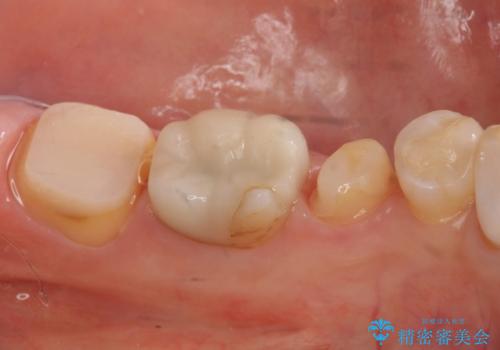

1. 昔いれたクラウンが割れたので金属の被せ物を入れたいの治療前